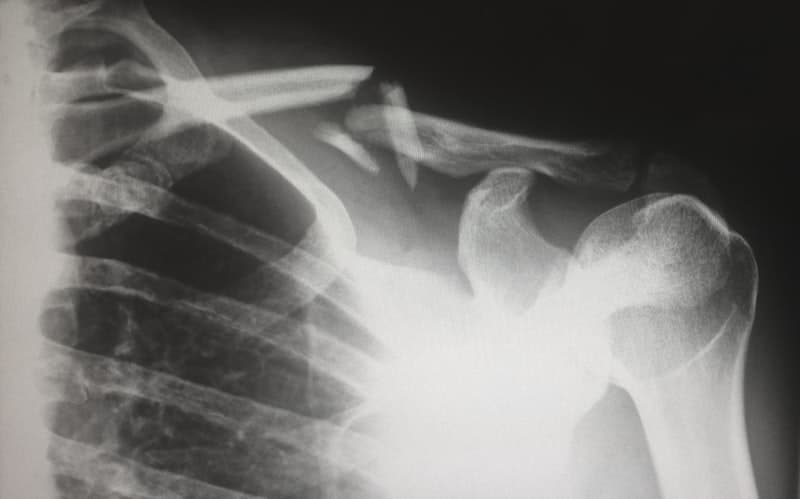

Lesión del cartílago (labrum) en el hombro o la cadera, que causa dolor, inestabilidad y movimiento limitado.

Rigidez y movimiento reducido del hombro debido a la inflamación de la cápsula del hombro.

Condición donde el movimiento del hombro causa compresión de tendones o bursa.

Condición del hombro donde los tendones del manguito rotador están irritados o inflamados.